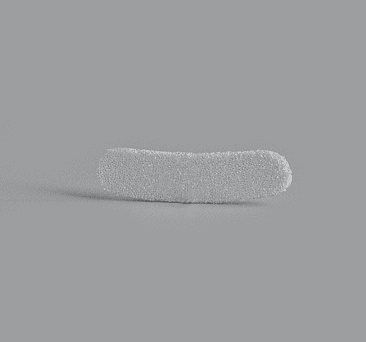

AIRO Implnat